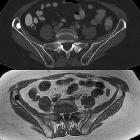

Osteom in den Beckenknochen

Osteom Radiopaedia • CC-by-nc-sa 3.0 • de

The imaging appearance reflects the underlying pathology, with ivory osteomas appearing as very radiodense lesions, similar to the normal cortex, whereas mature osteomas may demonstrate central marrow.